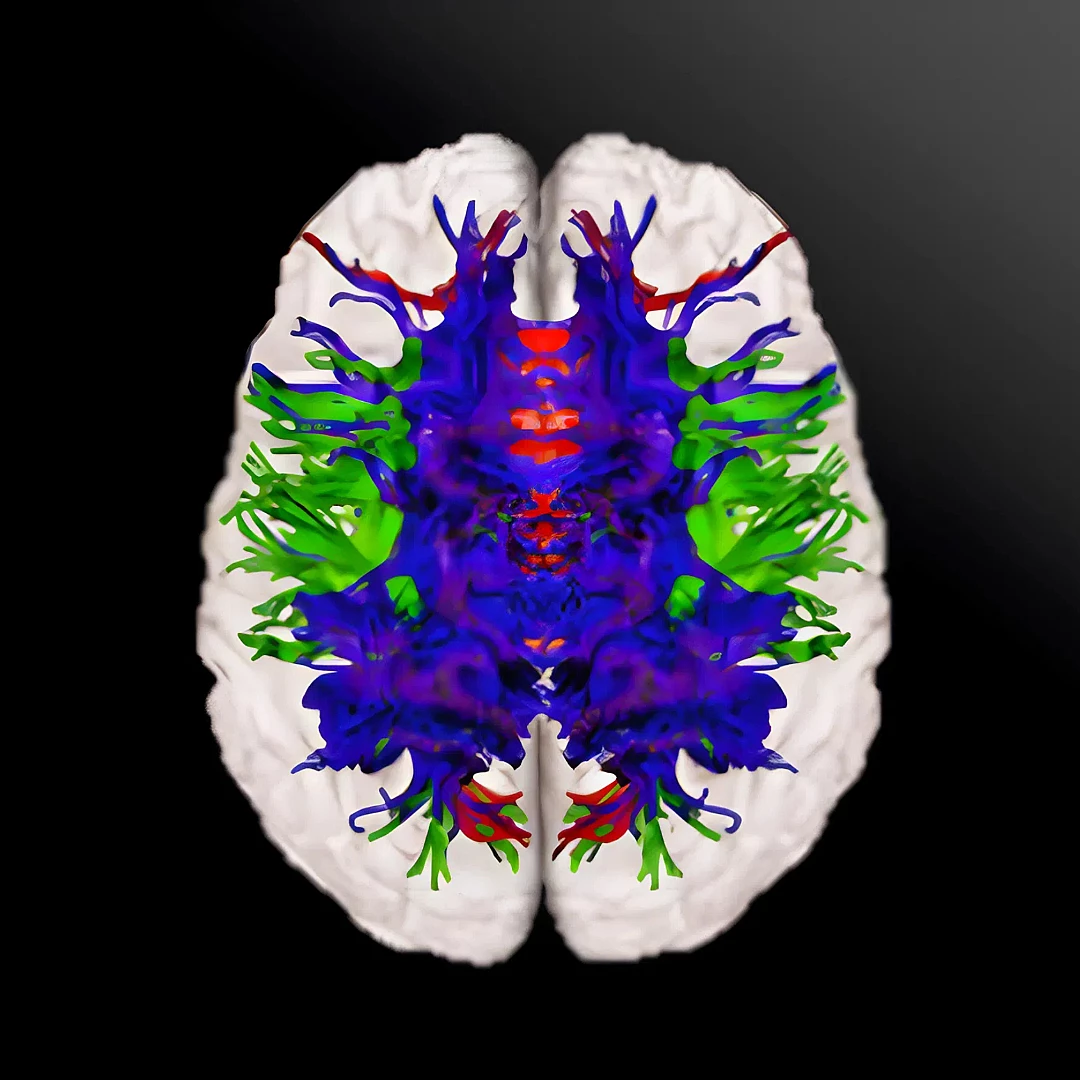

MRI Tractography

MRI Tractography visualizes the brain’s white matter pathways by tracking water movement along neural fibers. It’s crucial for mapping brain connectivity and planning precise neurosurgical interventions.